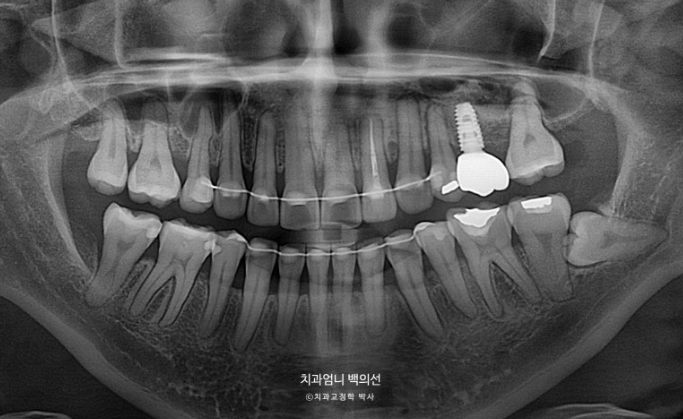

엑스레이상 좌측 위 첫번째 작은어금니 쪽으로 두번째 작은어금니가 쓰러지며 공간이 없어진게 보입니다.

어금니 교합관계 2급 입니다.

치료 시작 1년 3개월차 결손된 큰어금니 공간이 충분히 확보가 되어 드디어 임플란트를 식립했습니다.

파란 화살표 임플란트가 들어가고 좌우 치아갯수가 맞아졌습니다. 덕분에 중심선도 개선하고 어금니 교합관계도 1급이 되었으며 앞니가 뒤로 쓰러진 옥니도 고칠 수 있었습니다.

1년 8개월에 걸친 재교정 기간동안 추가적인 치근흡수는 없었으며 치근 형행도는 처음보다 개선이 되었습니다.